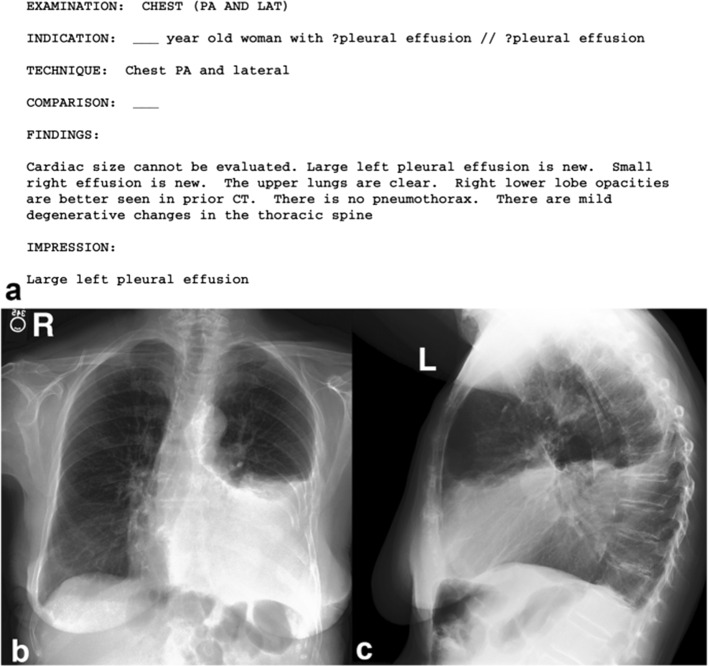

In general, medical reports are composed of different sections which we illustrate in Fig. 5 and detail in the following (Xiong et al. 2019; Li et al. 2018):

Indication: consists of a simple statement that provides some historical clinical information about the patient including gender, age as well as the reason for the study;

Tags: consist of pathological keywords which represent the critical information extracted from the findings;

Findings: consist of multiple sentences providing a detailed description of observations regarding different regions in the image, that may help to identify the disease or the abnormality;

Impression: consists of a single-sentence conclusion of the diagnosis which is established from the findings. It may summarize the findings and the patient’s clinical history. At the same time, it is considered to be the most important section of the medical report which is usually investigated by the clinicians (Tian et al. 2020).

Sometimes, another section is also available in the medical report to indicate whether the current imaging study is compared to prior scanning study or not (Singh et al. 2019) and is called the Comparison Section.

Fig. 5.

Different sections of the medical reports. Example from the IU X-Ray dataset, retrieved from (Jing et al. 2017)